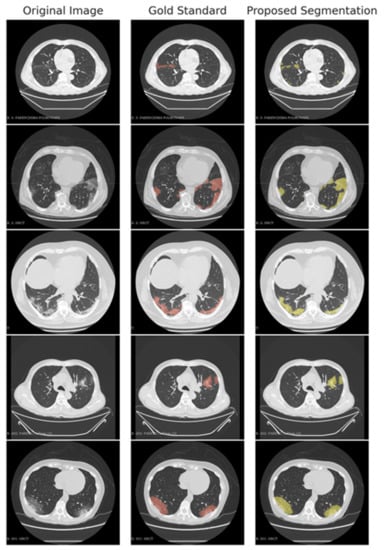

We show in Figure 2 the distribution of the individual scores (Sensitivity, Specificity, Precision, and F1 score). The scores were obtained by the average of the whole 15 scans (overall) on the 10 corona cases (CORONACASES OVERALL) and on the five gold standard (GOLD STD OVERALL). In Figure 3 and Figure 4, we show a visual comparison between the achieved segmentation and the ground truth labels (both for corona cases and the gold standard).

The examples reported in Figure 3 and Figure 4 show how the non-supervised segmentation method proposed in this paper is able to approximate the gold standard results with satisfactory results.

Figure 4. A comparison between the proposed automated segmentation pipeline and a gold standard segmentation manually performed by an expert radiologist.